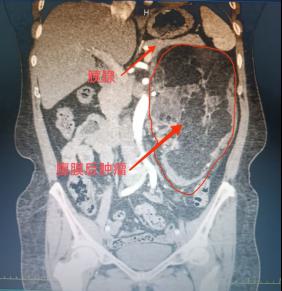

1个月前,闫女士在当地医院体检时,意外发现腹膜后藏着一枚巨大肿瘤。进一步检查显示,这枚肿瘤不仅体积较大,像“藤蔓”一样紧紧缠绕着胰腺、左肾及肾血管——这些都是人体腹部的“关键命脉”,稍有不慎就可能引发大出血,甚至危及生命。

“肿瘤位置深、体积大,还与重要脏器血管紧密粘连,单纯靠一个科室很难完成手术。”杨庆强仔细研读影像资料后,精准判断出手术的核心难点。这枚肿瘤不仅尺寸较大,还将左肾推挤移位,与肾血管、胰腺的边界模糊不清,任何操作失误都可能导致难以控制的血管损伤。